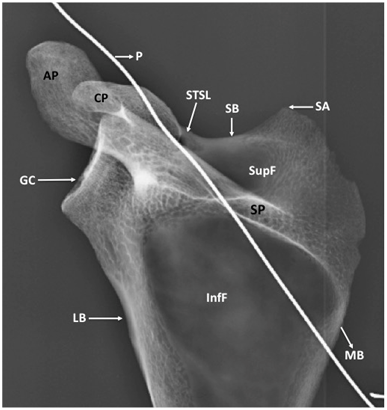

Figure 3 Anterior surface of bony scapula showing.

SSF, suprascapular foramen; STSL, superior transverse scapular ligament; P, probe in SSF; CP, coracoid process; AP, acromian process; GC, glenoid cavity; SupF, supraspinous fossa; LB, lateral border of scapula; SB, superior border of scapula; B, body of scapula

The circumference of the bony foramen was 17mm. Its superior margin was made of ossified STSL. The body of scapula constituted the inferior and medial margin. Root of coracoid process formed the lateral margin of the foramen. The maximum vertical diameter of the foramen was 7mm and the maximum transverse diameter was 4mm. The SSF was oval in shape. It was not present at the usual site but instead presented at the root of coracoid process. The margins of SSF were smooth and the foramen formed a communication between supraspinous and subscapular fossa. This was confirmed by passing a probe through the foramen. The ossified STSL, forming the superior margin of the SSF was oblique and fan shaped. It converted the suprascapular notch into a foramen. The width of STSL at the root of coracoid process was 3mm and its width at the lateral most end of superior border of scapula was 5mm. The patency of SSF was established by taking a radiological picture after putting a probe through the foramen (Figure 5) (Figure 6).